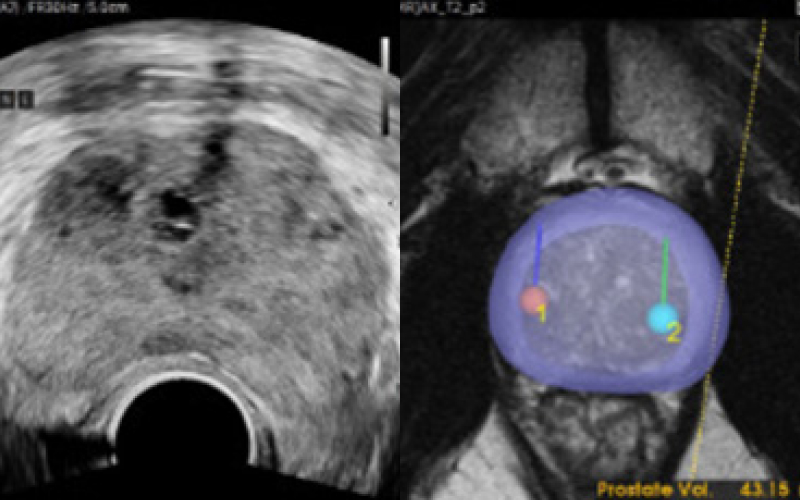

전립선을 자동으로 분석해 경계 분할

기존 검사는 병변 유무와 관계없이 12군데를 무작위로 채취해 정확도가 낮고 재검 가능성이 높았습니다. 하지만 MR 퓨전 조직검사는 병변을 직접 겨냥해 조직을 채취하므로 진단율이 크게 향상되었습니다.